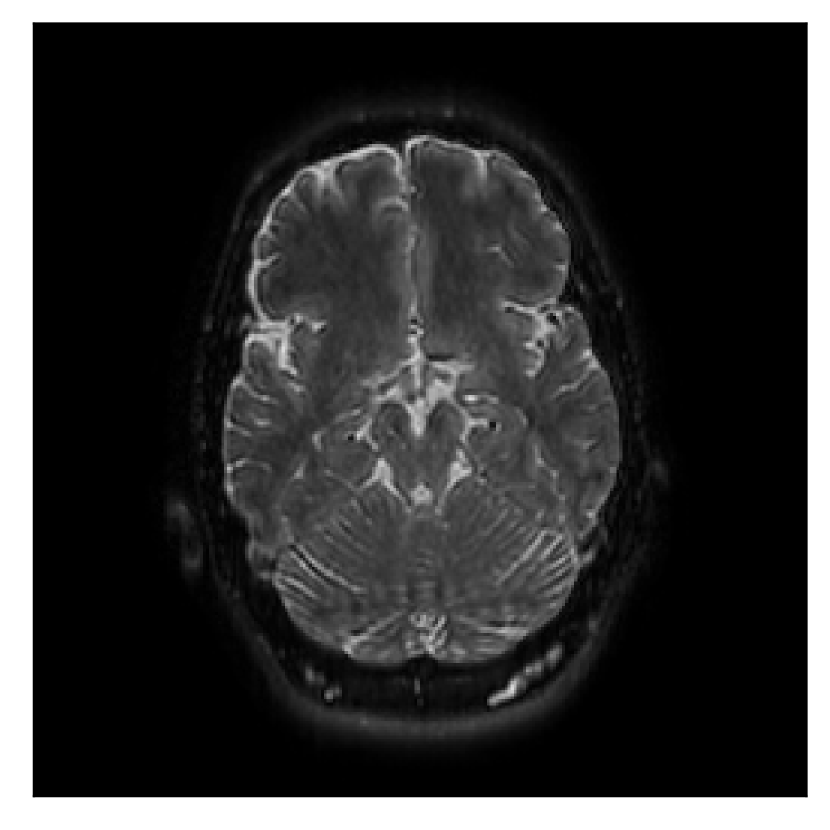

4.1 Experiment 1: robustness test

We gather the results for the robustness test described in Section 3.1 (volunteer 1) in Figures 2, 4, and 6 for motion corruption mechanisms associated to one, two, and five changes of position, respectively. Furthermore, we juxtapose the corrected images with varying degrees of corruption in Figure 8. We observe that the proposed method consistently ameliorates the corrupted scan. The quality indexes based on PSNR and SSIM show only a modest decrease in correction quality as a function of motion complexity (Figure 8).

| Section 3.1, Figure 2 | Sagittal | 23.94 | 27.95 | 0.7068 | 0.7936 |

| Coronal | 26.66 | 29.82 | 0.7653 | 0.8332 | |

| Axial | 25.40 | 30.16 | 0.7616 | 0.8490 | |

| Section 3.1, Figure 2 | T2-FLAIR | Completely corrected | Some blurring | No additional artifacts | Good grey white matter differentiation |

Sagittal

Coronal

Axial

Axial detail